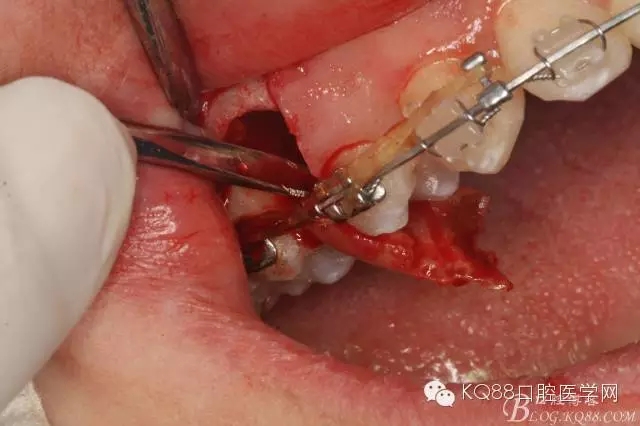

圖12. 做垂直切口+齦溝內(nèi)切口,形成角形瓣,暴露出15根面。

圖13. 用小球鉆去除約1mm牙槽骨,暴露15牙根面約5mm。